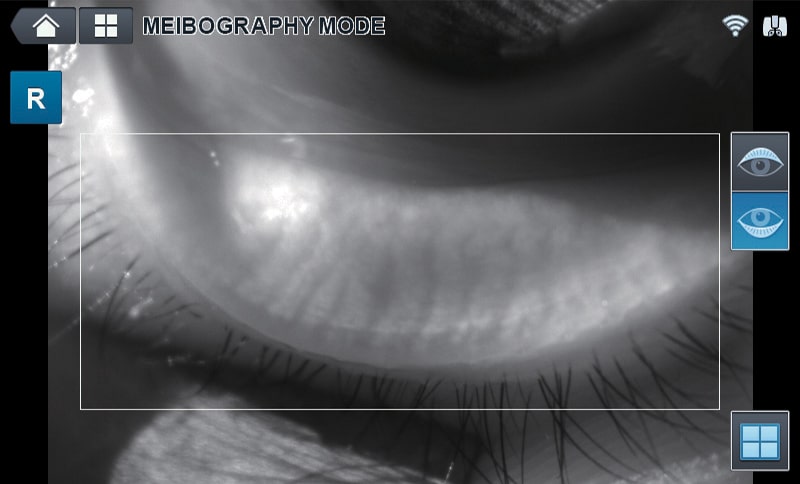

- TFBUT measurement & Meibography